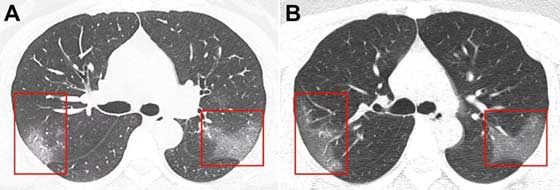

Çinli doktorlar, Radiology dergisinde, Çin’in Lanzhou kentinde 39 derece ateşle hastaneye kaldırılan 33 yaşındaki bir kadının bilgisayar tomografisini paylaştı.

İlk filmde, ‘buzlu cam efekti’ yaratan bir bulanıklık gözlemleniyor. Üç gün sonra yapılan ikinci filmde, etkilenen bölgenin genişlediği gözlemlenmekte.